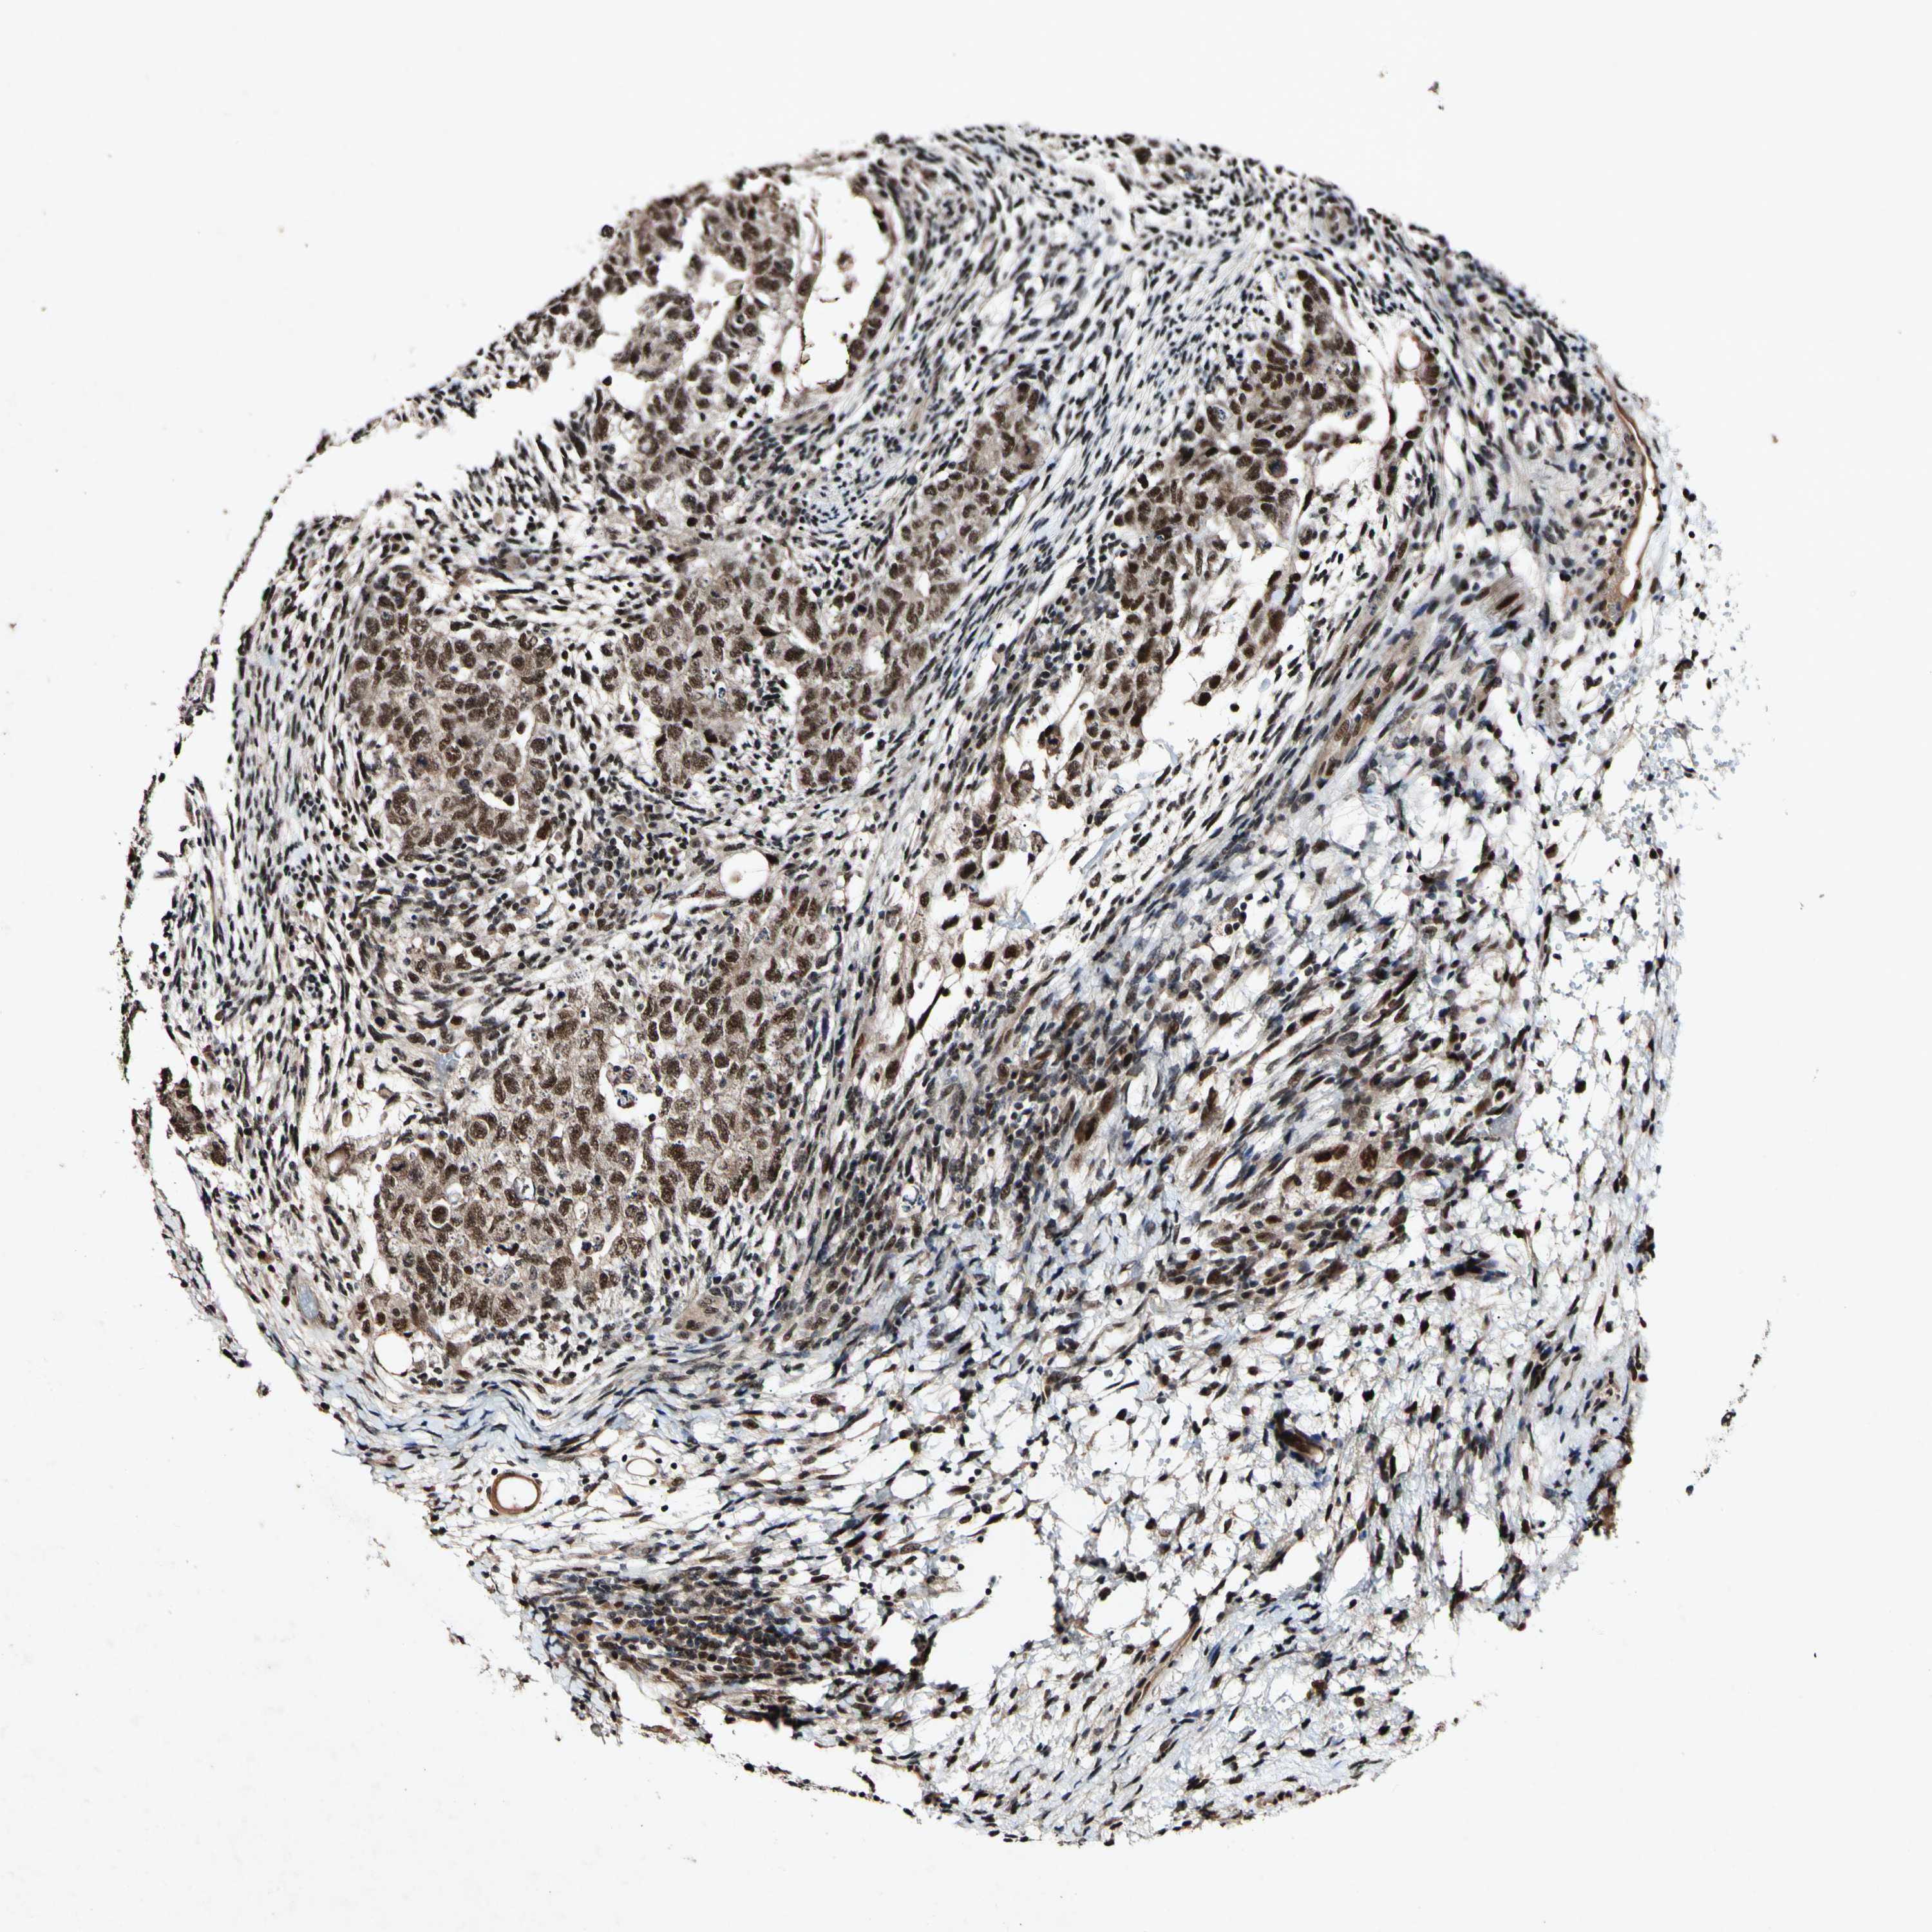

TESTIS CANCER - Protein expressioni

A mouse-over function shows sample information and annotation data. Click on an image to view it in a full screen mode. Samples can be filtered based on level of antibody staining by selecting one or several of the following categories: high, medium, low and not detected. The assay and annotation is described here.

Note that samples used for immunohistochemistry by the Human Protein Atlas do not correspond to samples in the TCGA dataset.

Antibody stainingi

Antibody staining in the annotated cell types in the current human tissue is reported as not detected, low, medium, or high, based on conventional immunohistochemistry profiling in selected tissues. This score is based on the combination of the staining intensity and fraction of stained cells.

Each image is clickable and will lead to virtual microscopy that enables deeper exploration of all samples and also displays staining intensity scores, fraction scores and subcellular localization as well as patient and tissue information for each sample.

Antibody CAB009882

Carcinoma, Embryonal, NOS